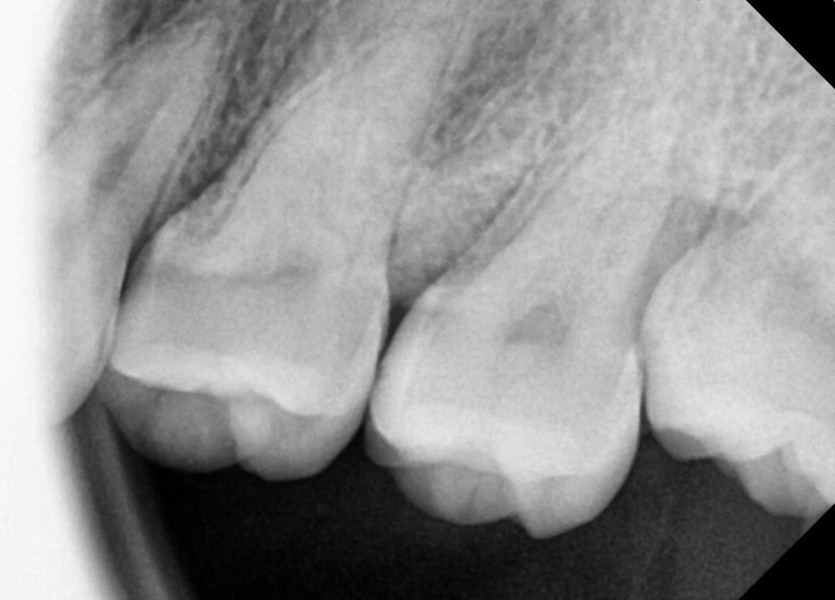

#28,38 사랑니 발치

구강 외과 전문의가 당일 발치했습니다.